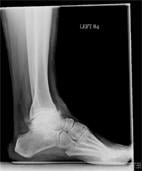

Mr. RS is a 54-year-old active gentleman who has had severe ankle pain over the past six years. He had an ankle injury while serving his country in the military and now has large bone spurs, joint space loss and significant loss of function, with difficulty walking on uneven ground. His primary care physician initiated a course of nonsteroidal anti-inflammatory medications, physical therapy and brace treatment to no avail: The pain continued to affect his life and activity level. After considering his options, Mr. RS elected to proceed with image-guided injection of local anesthetic and steroid mixture into his ankle joint. The goal of the image-guided injection was to improve his function, decrease his pain and diagnose the source of it.

As can be see on his X-rays (Figure 1, below), there was significant joint destruction in both the ankle (tibiotalar) and subtalar joints. Sequential targeted injection into first the ankle joint, followed (if needed) into the subtalar joint, would allow Mr. RS to “test-drive” any further intervention on these related, but separate, joints. Figure 2, above, shows the Navigator DS setup with the image-guided needle placing medication into the ankle joint. The procedure was completed in less than two minutes.

Mr. RS reported immediate 100 percent relief of pain, confirming symptomatic disease in only the ankle and not the subtalar joint. At three months he continues to be pain-free and back to full function.